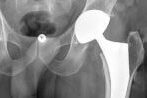

La prothèse de hanche

La prothèse de hanche est une solution médicale pour soulager la douleur et rétablir la mobilité chez les patients souffrant de problèmes articulaires au niveau de la hanche. Dans cet article, nous explorerons les avantages de la prothèse de hanche i vous résidez sur l’île de La Réunion et envisagez de bénéficier d’une mise en place de prothèse de hanche

La prothèse de hanche est une intervention chirurgicale qui vise à remplacer l’articulation de la hanche endommagée par une articulation artificielle. Cela permet de soulager la douleur chronique causée par l’arthrose, les fractures ou d’autres affections de la hanche. Une fois la prothèse en place, les patients retrouvent une meilleure mobilité, ce qui leur permet de mener une vie active et sans douleur.